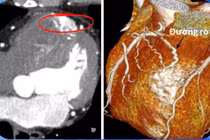

Dò động mạch vành là một tình trạng bất thường trong hệ thống mạch máu tim khiến lượng máu cung cấp cho cơ tim bị giảm, gây ra những triệu chứng như khó thở, đau tức ngực.